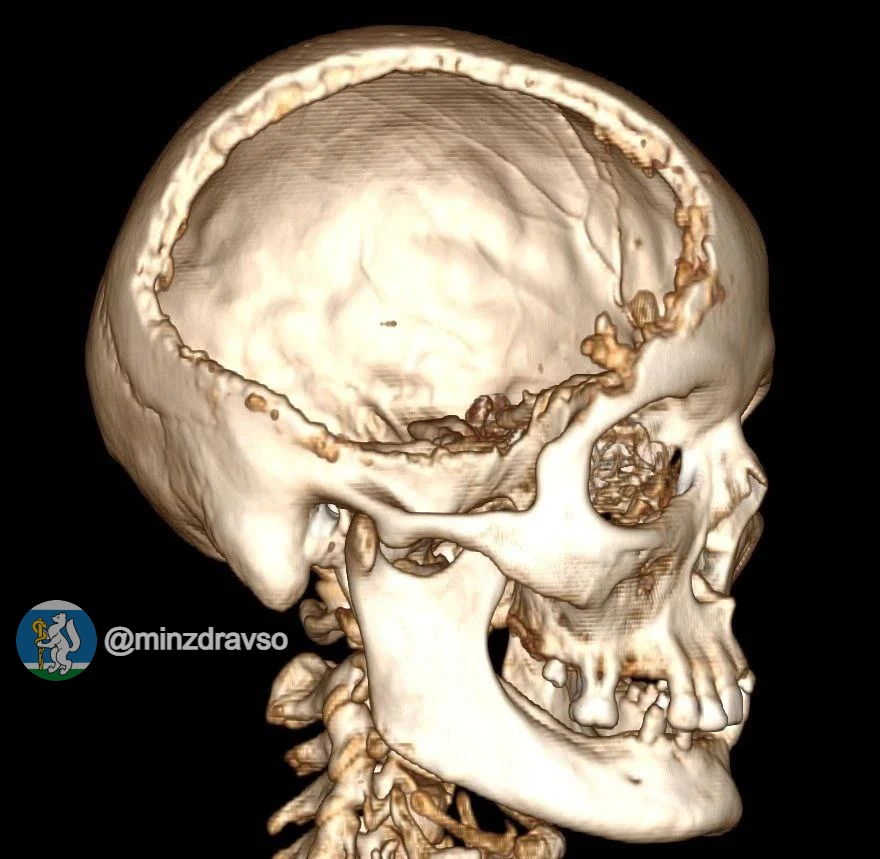

🦴 Точность до миллиметра: как уральские онкологи возвращают полноценную жизнь после сложных диагнозов

Онкоортопедия — одно из самых сложных направлений в медицине. Здесь нельзя допустить ошибку: на кону не просто удаление опухоли, а возможность человека снова ходить, работать, жить полноценно. В Свердловском онкологическом диспансере развивается передовая технология, которая меняет правила игры: замена поражённых костных сегментов высокоточными индивидуальными имплантами.

🤖В настоящее время для пациентов моделируют индивидуальные импланты, которые затем изготавливают на производстве. С 2024 года профильные специалисты учреждения здравоохранения выполнили пять вмешательств с полным замещением имплантом удалённой костной ткани.

Одним из недавних подобных случаев стало выявление новообразования у свердловчанки спровоцировало патологический перелом бедренной кости при обычной домашней нагрузке. После углублённой диагностики было принято решение провести органосохраняющую операцию, в ходе которой 20 сантиметров поражённой кости заменили индивидуальным титановым эндопротезом, смоделированным медиками на основе послойной компьютерной томографии и отпечатанным на заводе.

(на нашем фото)

🔥После успешной операции, которая длилась 5,5 часов, пациентка находится в раннем реабилитационном периоде и, несмотря на сложность и обширный объём хирургического вмешательства, передвигается самостоятельно.